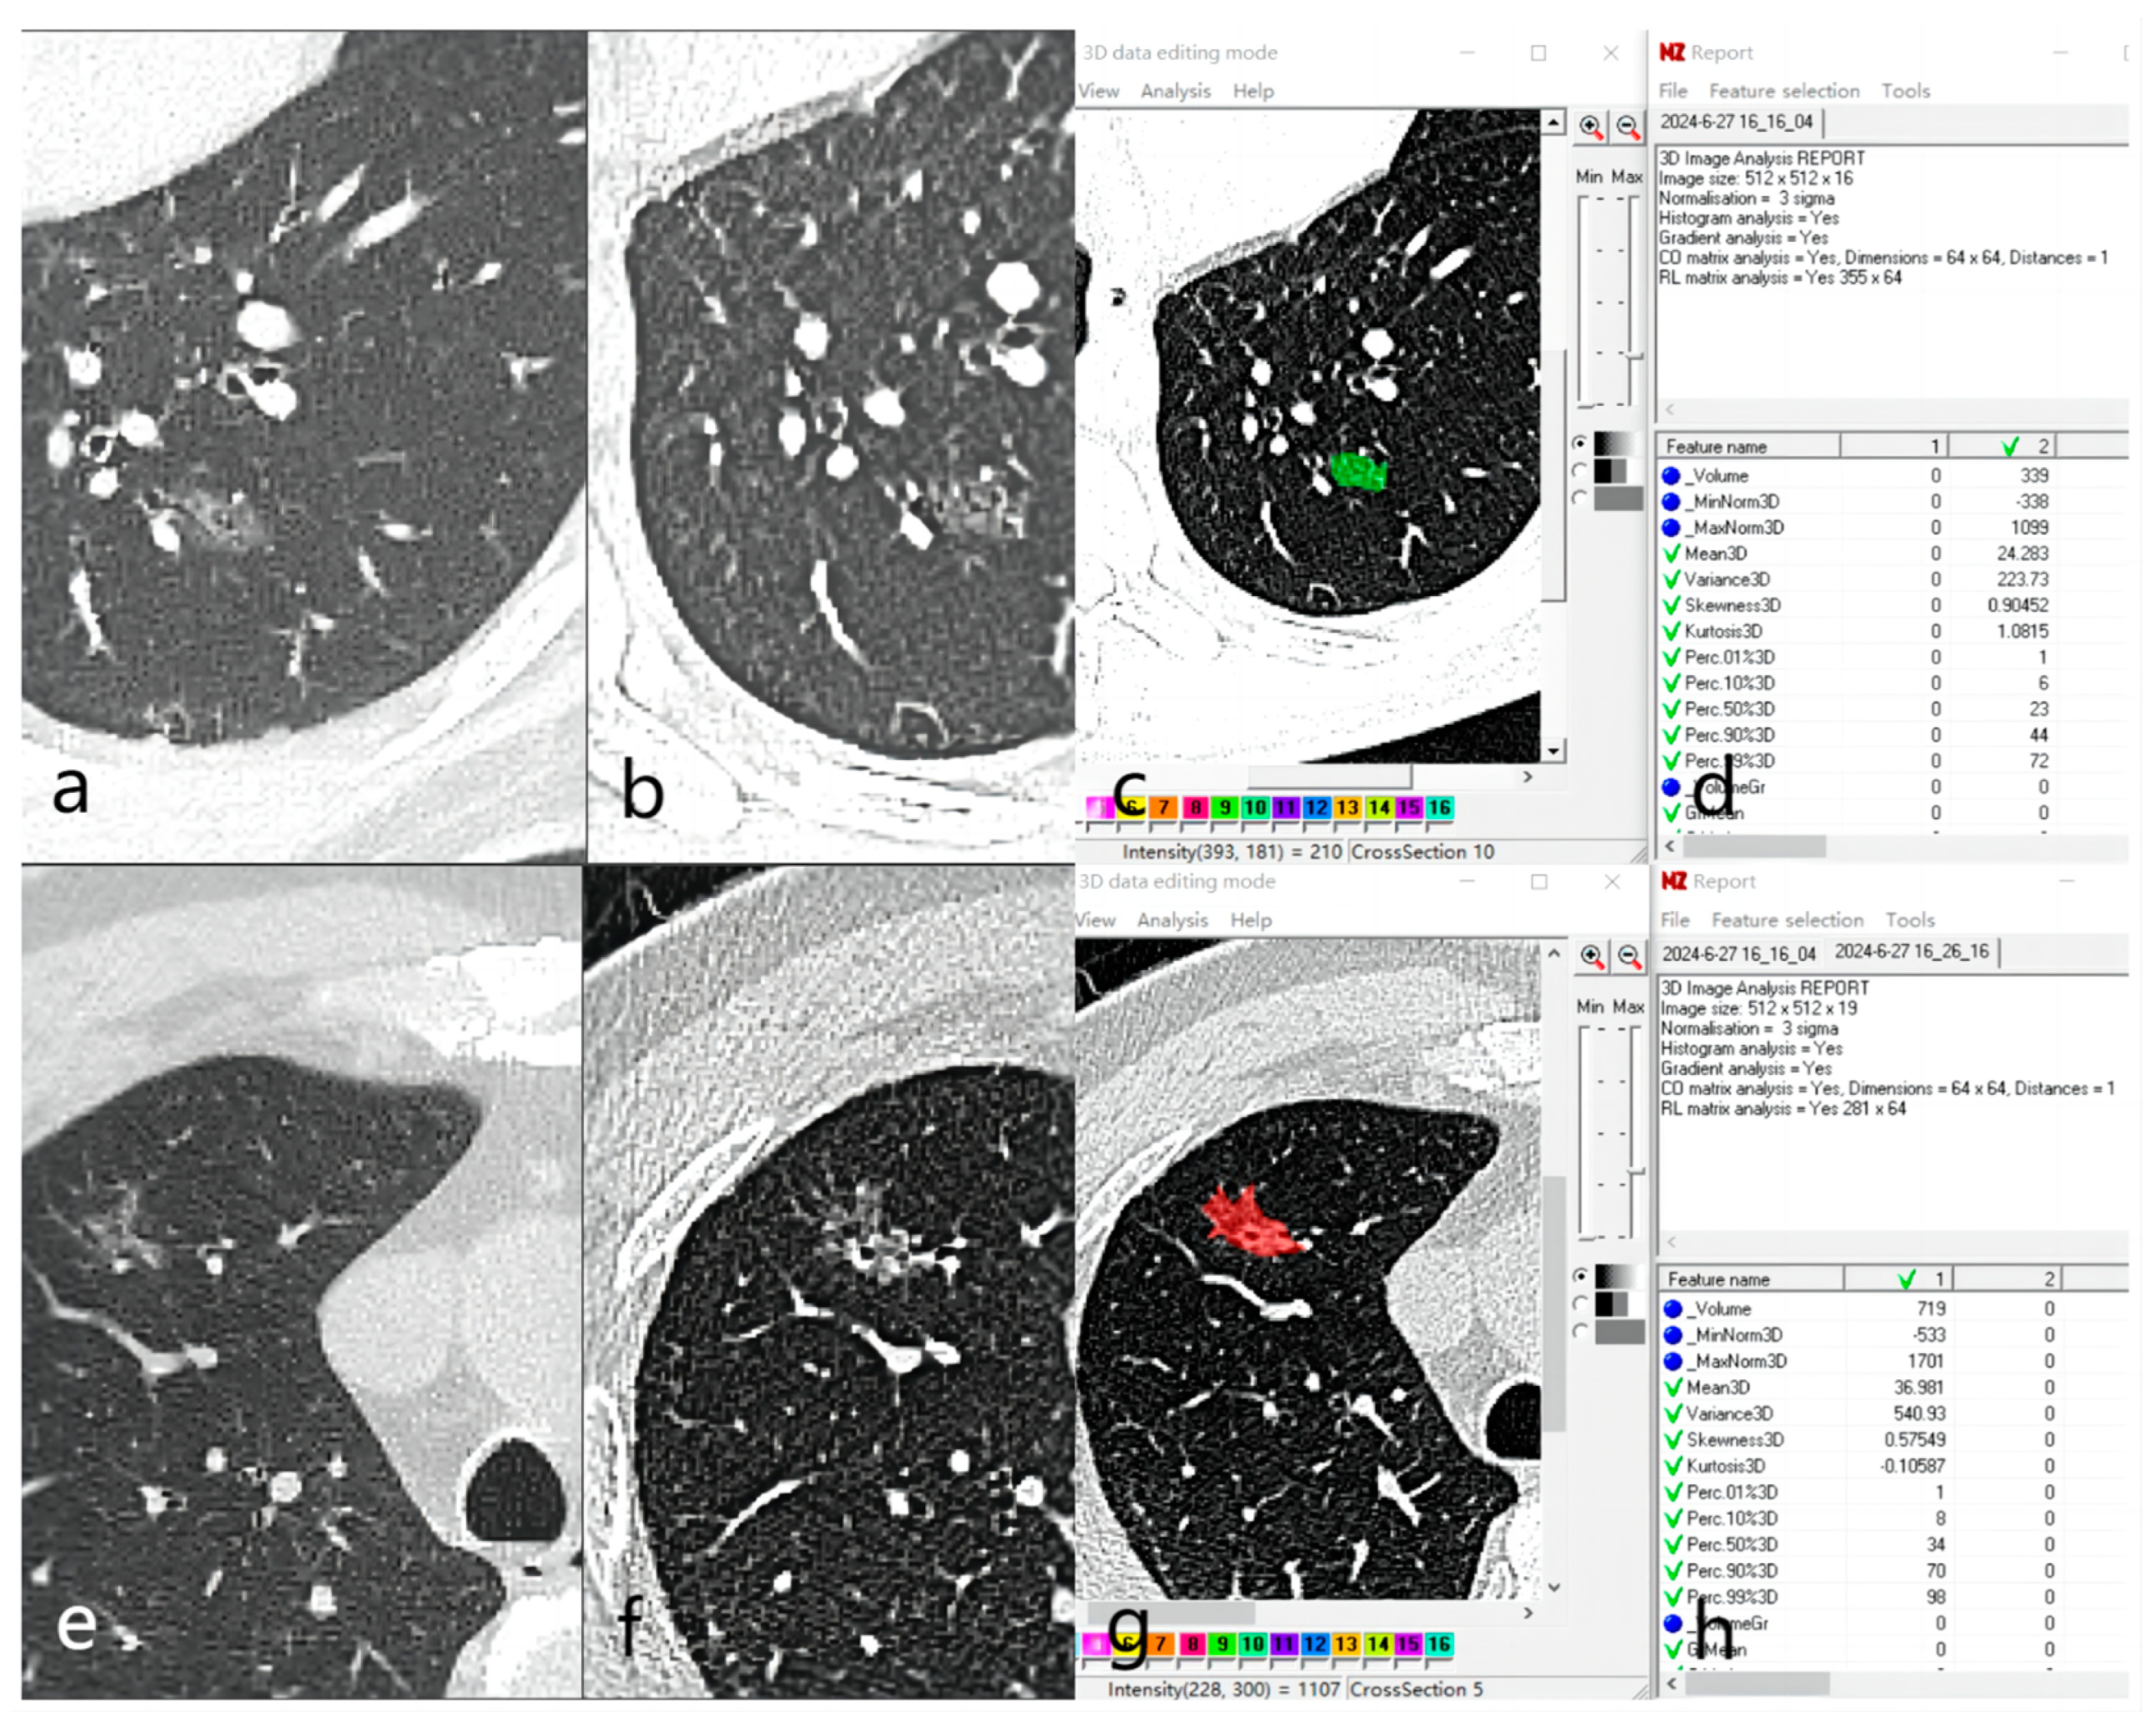

2.3. Image Analysis and Feature Extraction